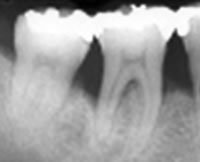

歯の周囲の歯ぐきの腫れが強くなり、歯を支えている骨が吸収し始めてきます。

中等度歯周炎

歯周ポケット 4~7mm

歯を支えている骨がさらに吸収して、歯が動揺を始めます。

重度歯周炎

歯周ポケット 6mm以上

歯を支えている骨がさらに吸収して、歯が動揺を始めます。

侵襲性歯周炎

思春期前から35歳までに永久歯列の数歯あるいは多数歯に発症し、アタッチメントレベルの低下と歯槽骨吸収の急速な進行を特徴とする疾患です。